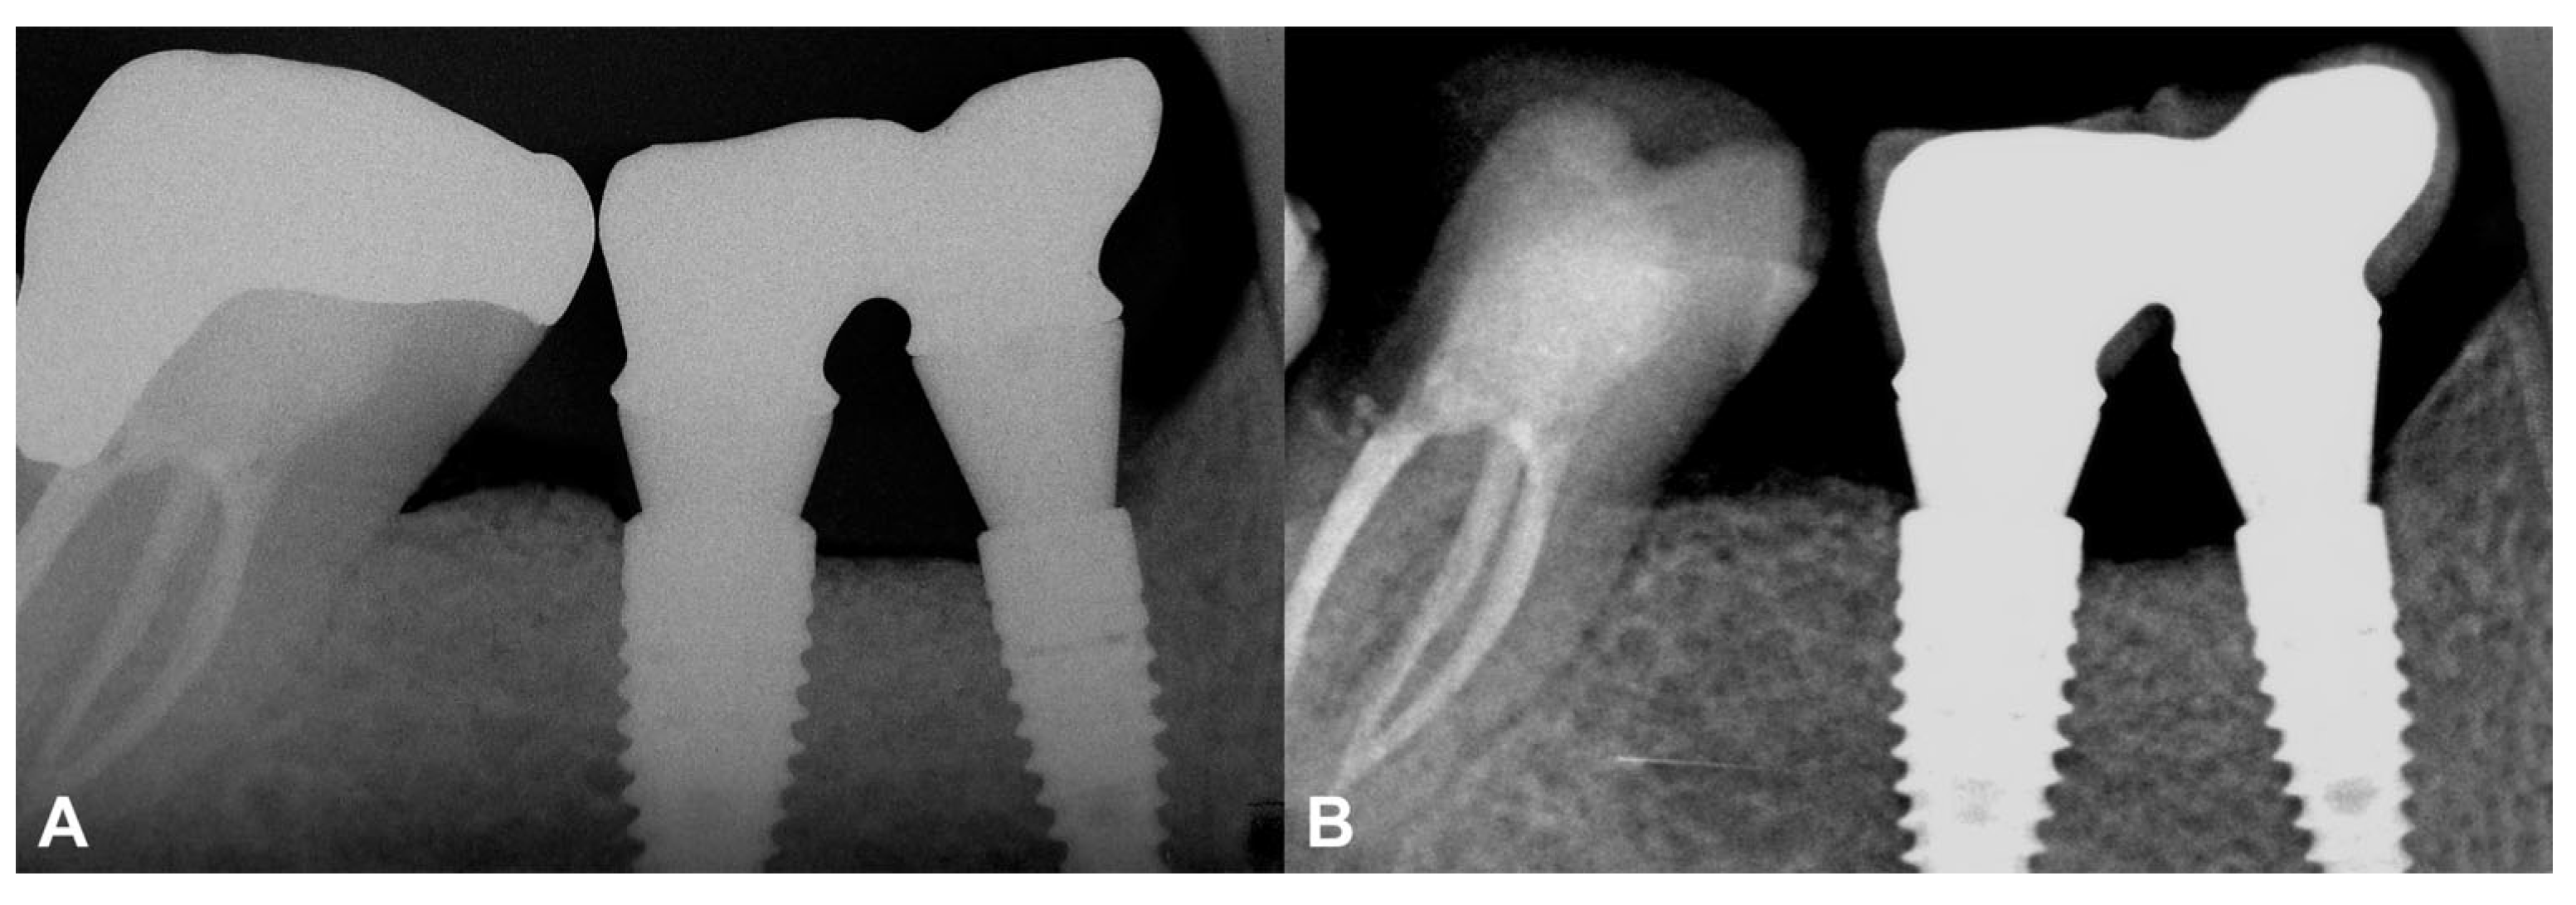

3.1.1. Baseline Clinical Situation

3.2.1. Baseline Clinical Situation